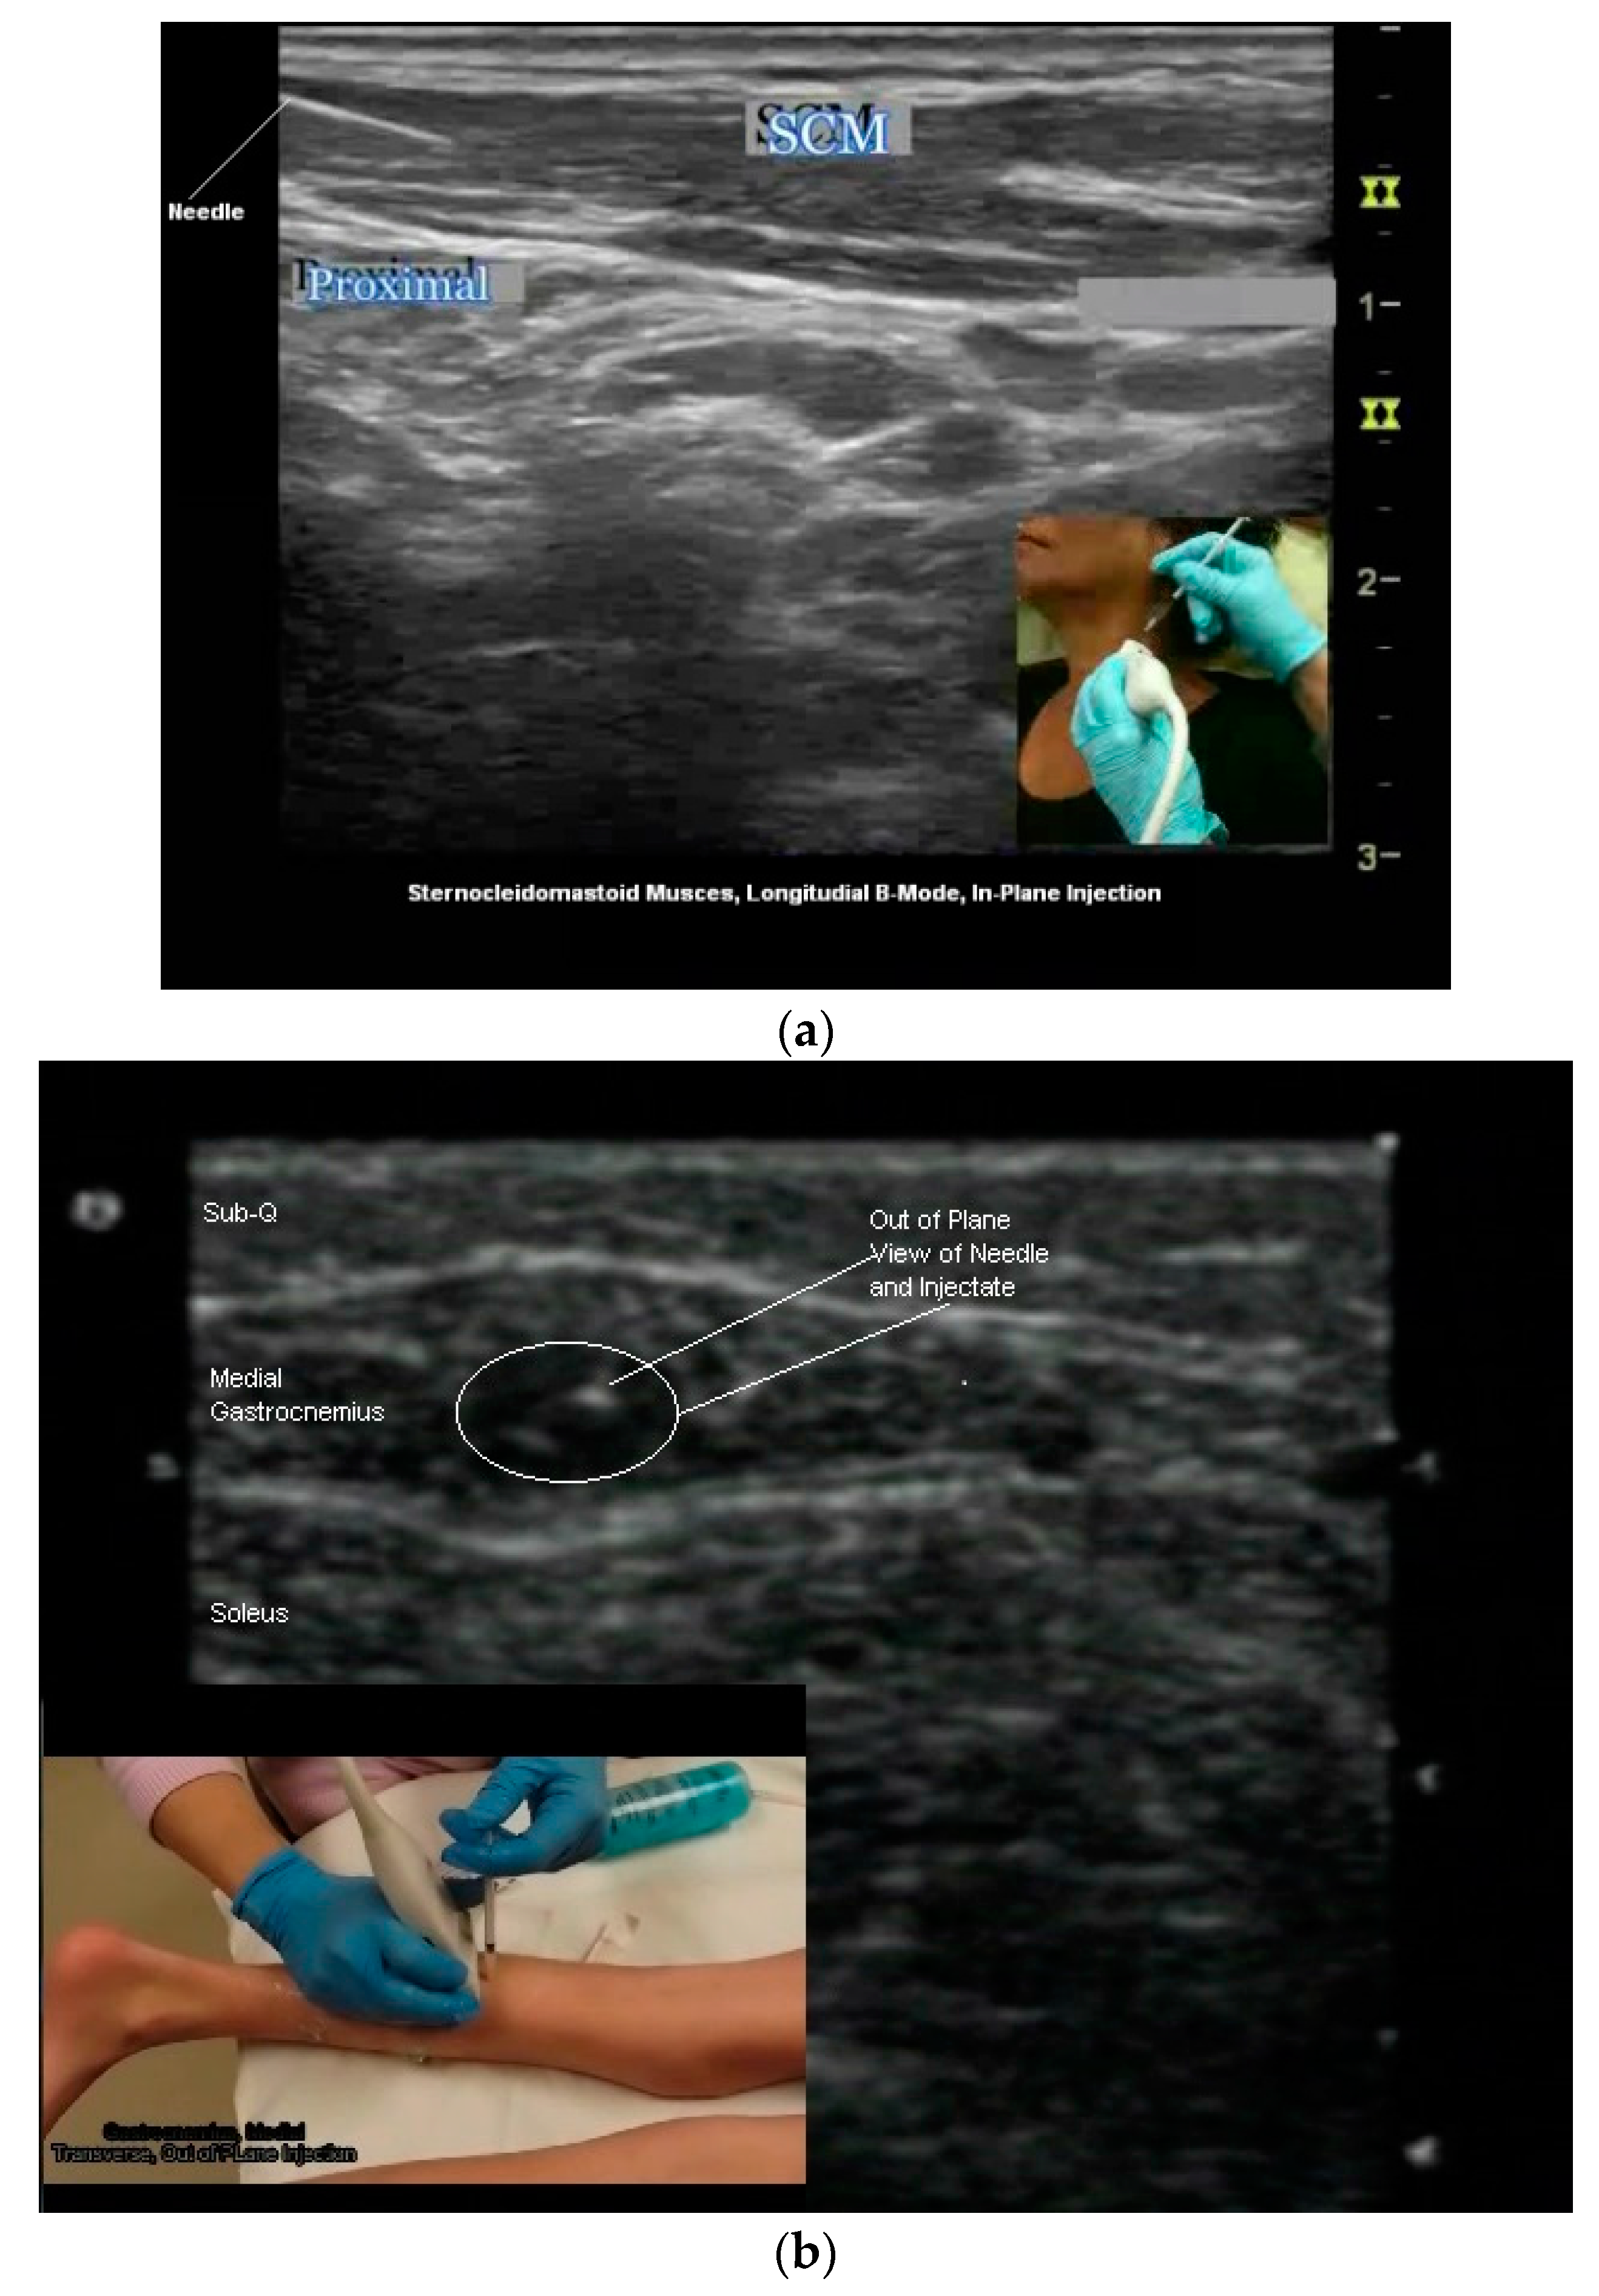

- In Plane Technique (IPT). When using an IPT the needle is inserted along the length of the transducer (Figure 6b and Figure 7a). With the IPT, the entire needle and its tip is visualized, an advantage over the OPT. However, this technique can be challenging to perform because the sonographer must keep the needle within the narrow US beam. Another challenge is that optimal needle visualization requires that the needle be inserted and maintained in an orientation perpendicular to the US beam Figure 8a. When inserted at a steep or oblique angle, visualization of the needle may be lost due to needle anisotropy [24,50,54] (Figure 8b).

- To keep the needle perpendicular to the US beam requires needle insertion to be at a flat angle relative to the transducer (Figure 8a). For superficial structures, such as the sternocleidomastoid muscle, this is easily accomplished. When targeting deeper muscles/structures, the needle must be inserted at some distance from the transducer to maintain an angle that minimizes anisotropy. This often requires a larger gauge, longer needle.

- The oblique approach may also be problematic when targeting some structures (such as anterior or middle scalene muscles) where an indirect path to the target may traverse regions with large vessels and nerves which must be avoided Figure 5a,b.